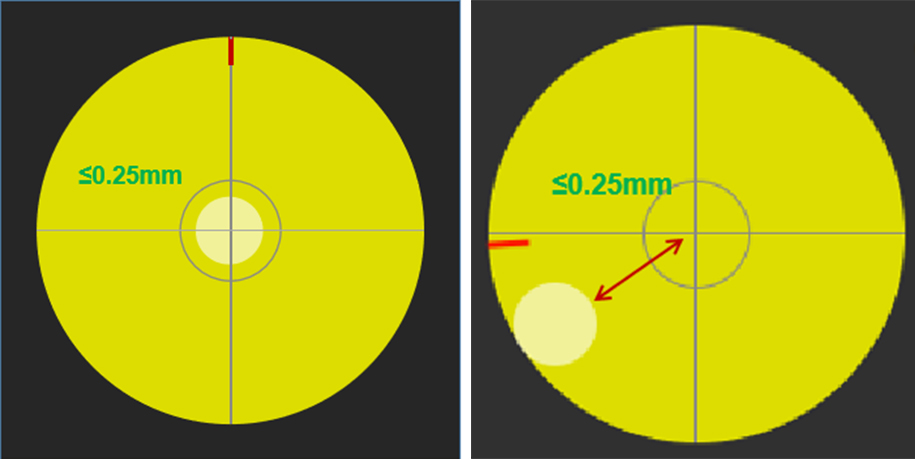

Positioning Accuracy and Repeatability

Accuracy: Supports a variety of tools for selecting stimulation targets, which can set stimulation targets according to brain functional areas, also can record and add current stimulation targets, and automatically set the relevant optimal coil positions.

Repeatability:The target information and coil position information of the latest stimulation can be saved, and the coil can be quickly repositioned according to the saved information in the subsequent treatment and research to ensure that the coil is in the same direction and angle as the previous stimulation, and the positioning error of the stimulation target does not exceed 0.25mm.